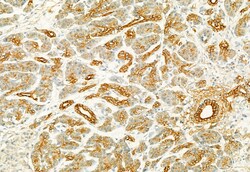

PLCE1 Polyclonal Antibody, Invitrogen™

Antibody detects endogenous levels of total PLCE1.

| Immunocytochemistry, Immunohistochemistry (Paraffin), Western Blot | |

| A synthesized peptide derived from human PLCE1(Accession Q9P212), corresponding to amino acid residues R2267-Q2302. | |